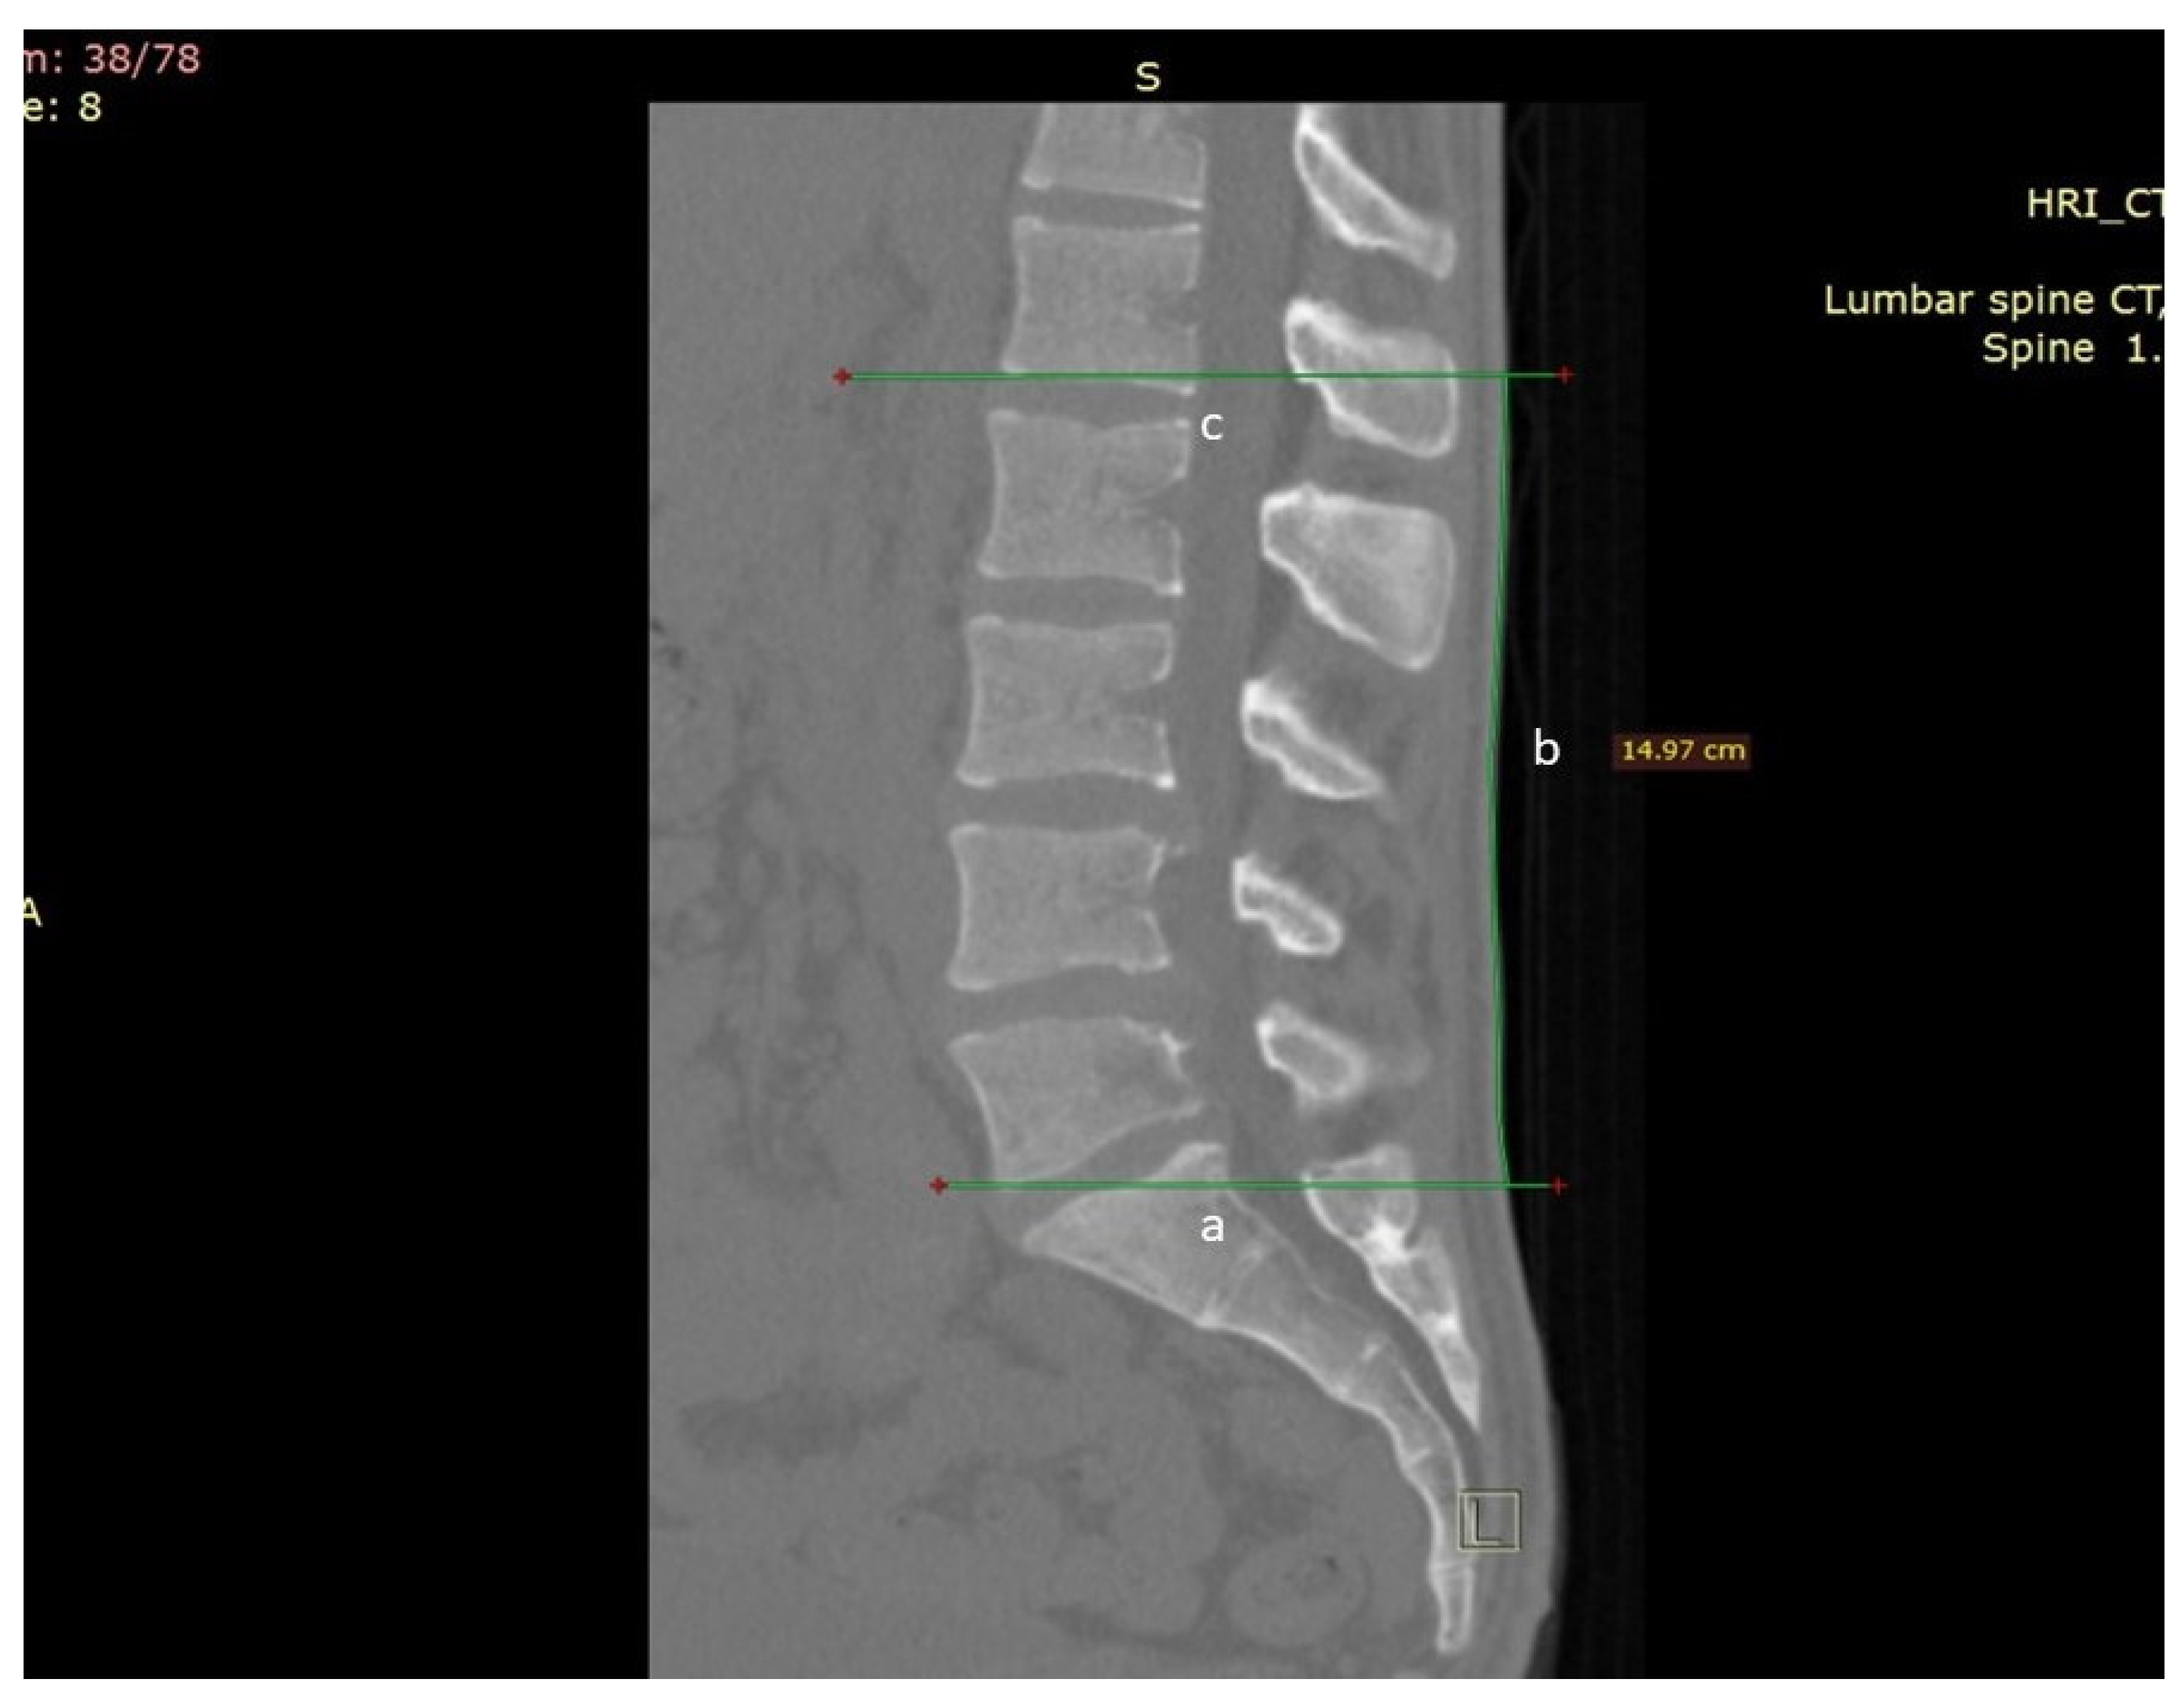

2. Methods